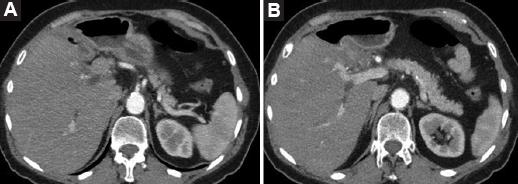

Tras la intervención en 2014, la paciente permaneció asintomática y sin evidencia de recidiva en los controles oncológicos practicados hasta que, en 2020, consultó en el departamento de urgencias por presentar ictericia indolora, coluria y acolia. En la analítica destacaban bilirrubina total 2.75 mg/dl, bilirrubina directa 2.01 mg/dl, aspartato aminotransferasa 406 U/l, alanina aminotransferasa 555 U/l, gamma glutamil transpeptidasa 10,999 U/l, fosfatasa alcalina 163 U/l, CEA 50,3 ng/ml y CA 19.9 2.48 U/ml. En la tomografía computarizada (Fig. 1) se puso de manifiesto una lesión extrínseca de 23 × 15 mm en la unión de las vías biliares principales junto con dilatación de la vía biliar derecha. En la colangiopancreatografía retrógrada endoscópica (CPRE) se observó una estenosis larga que afectaba al conducto hepático derecho con dilatación de las vías biliares principales proximales a la estenosis (Fig. 2), por lo que se decidió colocar una prótesis plástica. La paciente presentó, como complicación, una pancreatitis pos-CPRE que evolucionó de forma favorable con tratamiento conservador.

Figura 1 Tomografía computarizada que muestra una lesión de 2 cm en la vía biliar (A) y dilatación de vía biliar intrahepática derecha (B).